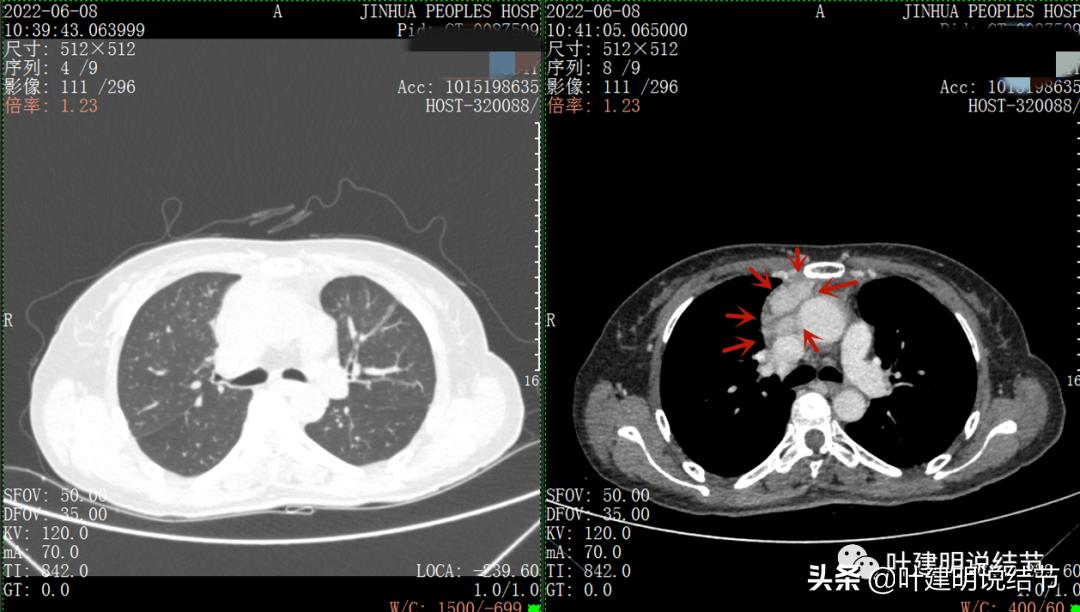

以下图片左侧是肺窗,右侧是纵隔窗。红色箭头示病灶,桔色箭头示无名静脉,黄色箭头示支气管,砖色箭头示上腔静脉,蓝色箭头示主动脉,紫色箭头示肺动脉。

病灶占据前纵隔从上到下全程,多中心,密度不均,对心脏与大血管有压迫,没有明显侵犯

病灶表面不平,中间有坏死

上图示最大横断位达5厘米